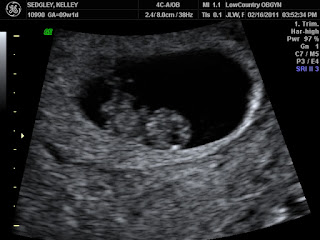

One year ago today was one of the Top 10 happiest Days of my life…. I am literally counting on one two hands to make sure this is an accurate statement. Yes it is!! Today is the day I found out we were having

| Due September 20, 2011 |